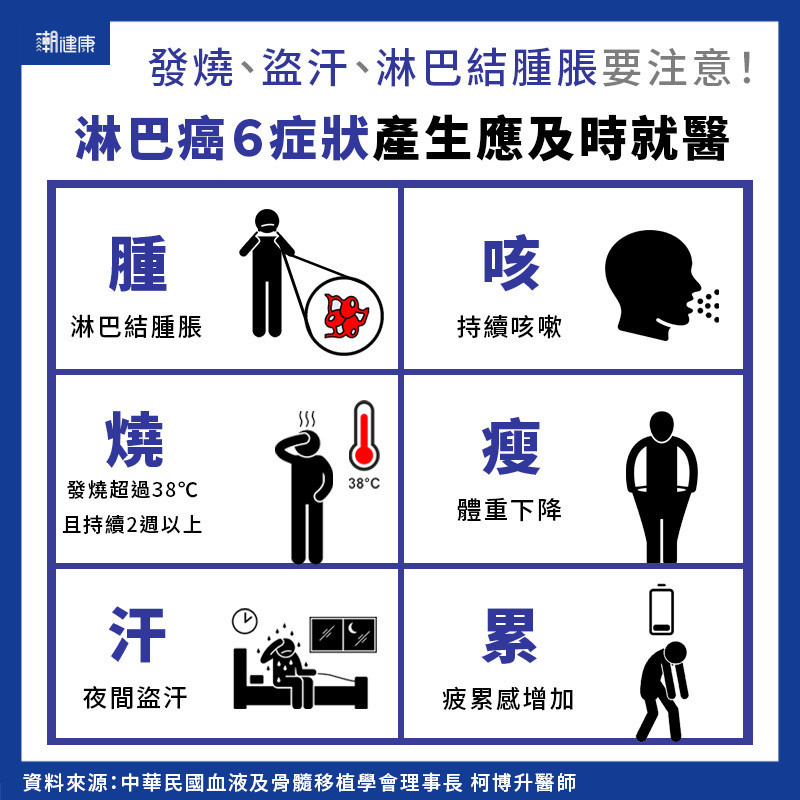

發燒2個月確診! 醫揭淋巴癌6症狀:盜汗疲累、淋巴腫莫輕忽 | 潮健康 COOL HEALTH | 集結最新健康、潮流、知識的新媒體平台

淋巴癌早期的6大警訊! | Heho健康

淋巴癌早期症狀有哪4點 – 每日頭條

發燒2個月確診! 醫揭淋巴癌6症狀:盜汗疲累、淋巴腫莫輕忽 | 潮健康 COOL HEALTH | 集結最新健康、潮流、知識的新媒體平台